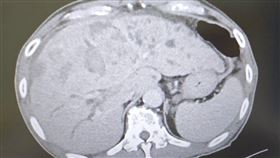

59歲男罹肝癌 1年後「12公分腫瘤」竟沒了

罹患肝癌不代表走入絕境,胃腸肝膽科醫師錢政弘分享,過...

2026/01/26 10:43